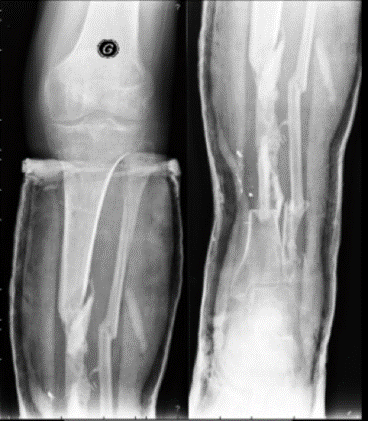

Currently 15 months after bone reconstruction (23 months post-accident), the patient is full weight bearing with complete recovery of skin and bone as shown in the following pictures (Figures 15, 16, 17).

Figure 15: Currently 15 months after bone reconstruction (23 months post-accident), the patient is full weight bearing with complete recovery of skin and bone.

Figure 16: Currently 15 months after bone reconstruction (23 months post-accident), the patient is full weight bearing with complete recovery of skin and bone.

Figure 17: Currently 15 months after bone reconstruction (23 months post-accident), the patient is full weight bearing with complete recovery of skin and bone.